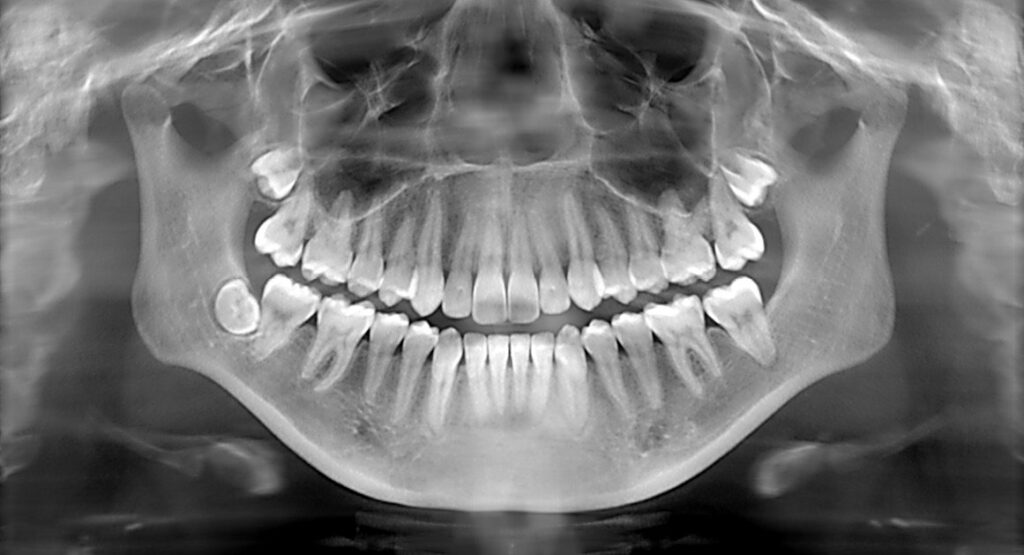

X-rays give us a clear picture of what’s happening beneath the surface of your teeth and gums that we cannot visually see. They help us find small cavities, check the health of your roots and jawbone, and detect issues before they become painful or more complicated to treat. Simply put, they allow us to take care of your oral health in the most accurate and preventive way possible.